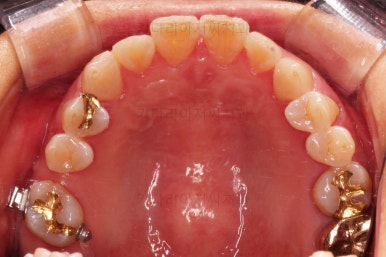

어금니를 뒤로 밀어주기 위해서 미니스크로와 브라켓, 철사를 이용해줍니다.

중간중간 장치 디자인이나 미니스크류의 위치를 바꿔주기도 합니다.

점점 자리가 확보되어가는게 보이시죠?

적절한 공간이 확보되었다고 판단되면 임플란트를 식립합니다.

임플란트가 뼈에 단단히 붙은 몇개월의 시간동안 교정치료를 좀 더 마무리 해주고요.

임플란트 머리 부분까지 완성이 되었습니다.